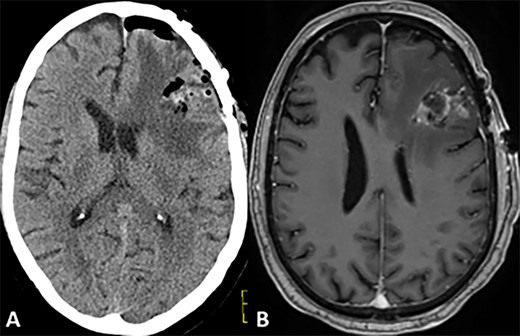

CASE

MRI scans indicating new metastatic lesions of the bilateral frontal lobes and right cerebral peduncle.